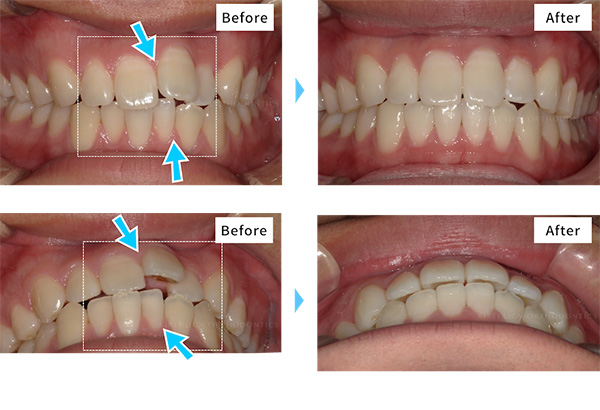

-

- 治療期間

- 約6ヶ月(キレイラインを4回実施)

- 治療費用

- 160,000円(税込176,000円)

-

No

5310308

-

症状

ガタガタな歯

-

再診料

(4回) 12,000円 (税込13,200円)

-

追加治療

拡大床(上下)80,000円 (税込88,000円)

- ※効果には個人差があります。※拡大床は、キレイライン矯正による矯正歯科治療の一環ではありません。患者様のご要望や症状により医師の判断のもと行われる「クリニックの治療」に該当しますので、詳細は提携クリニックに直接ご確認ください。